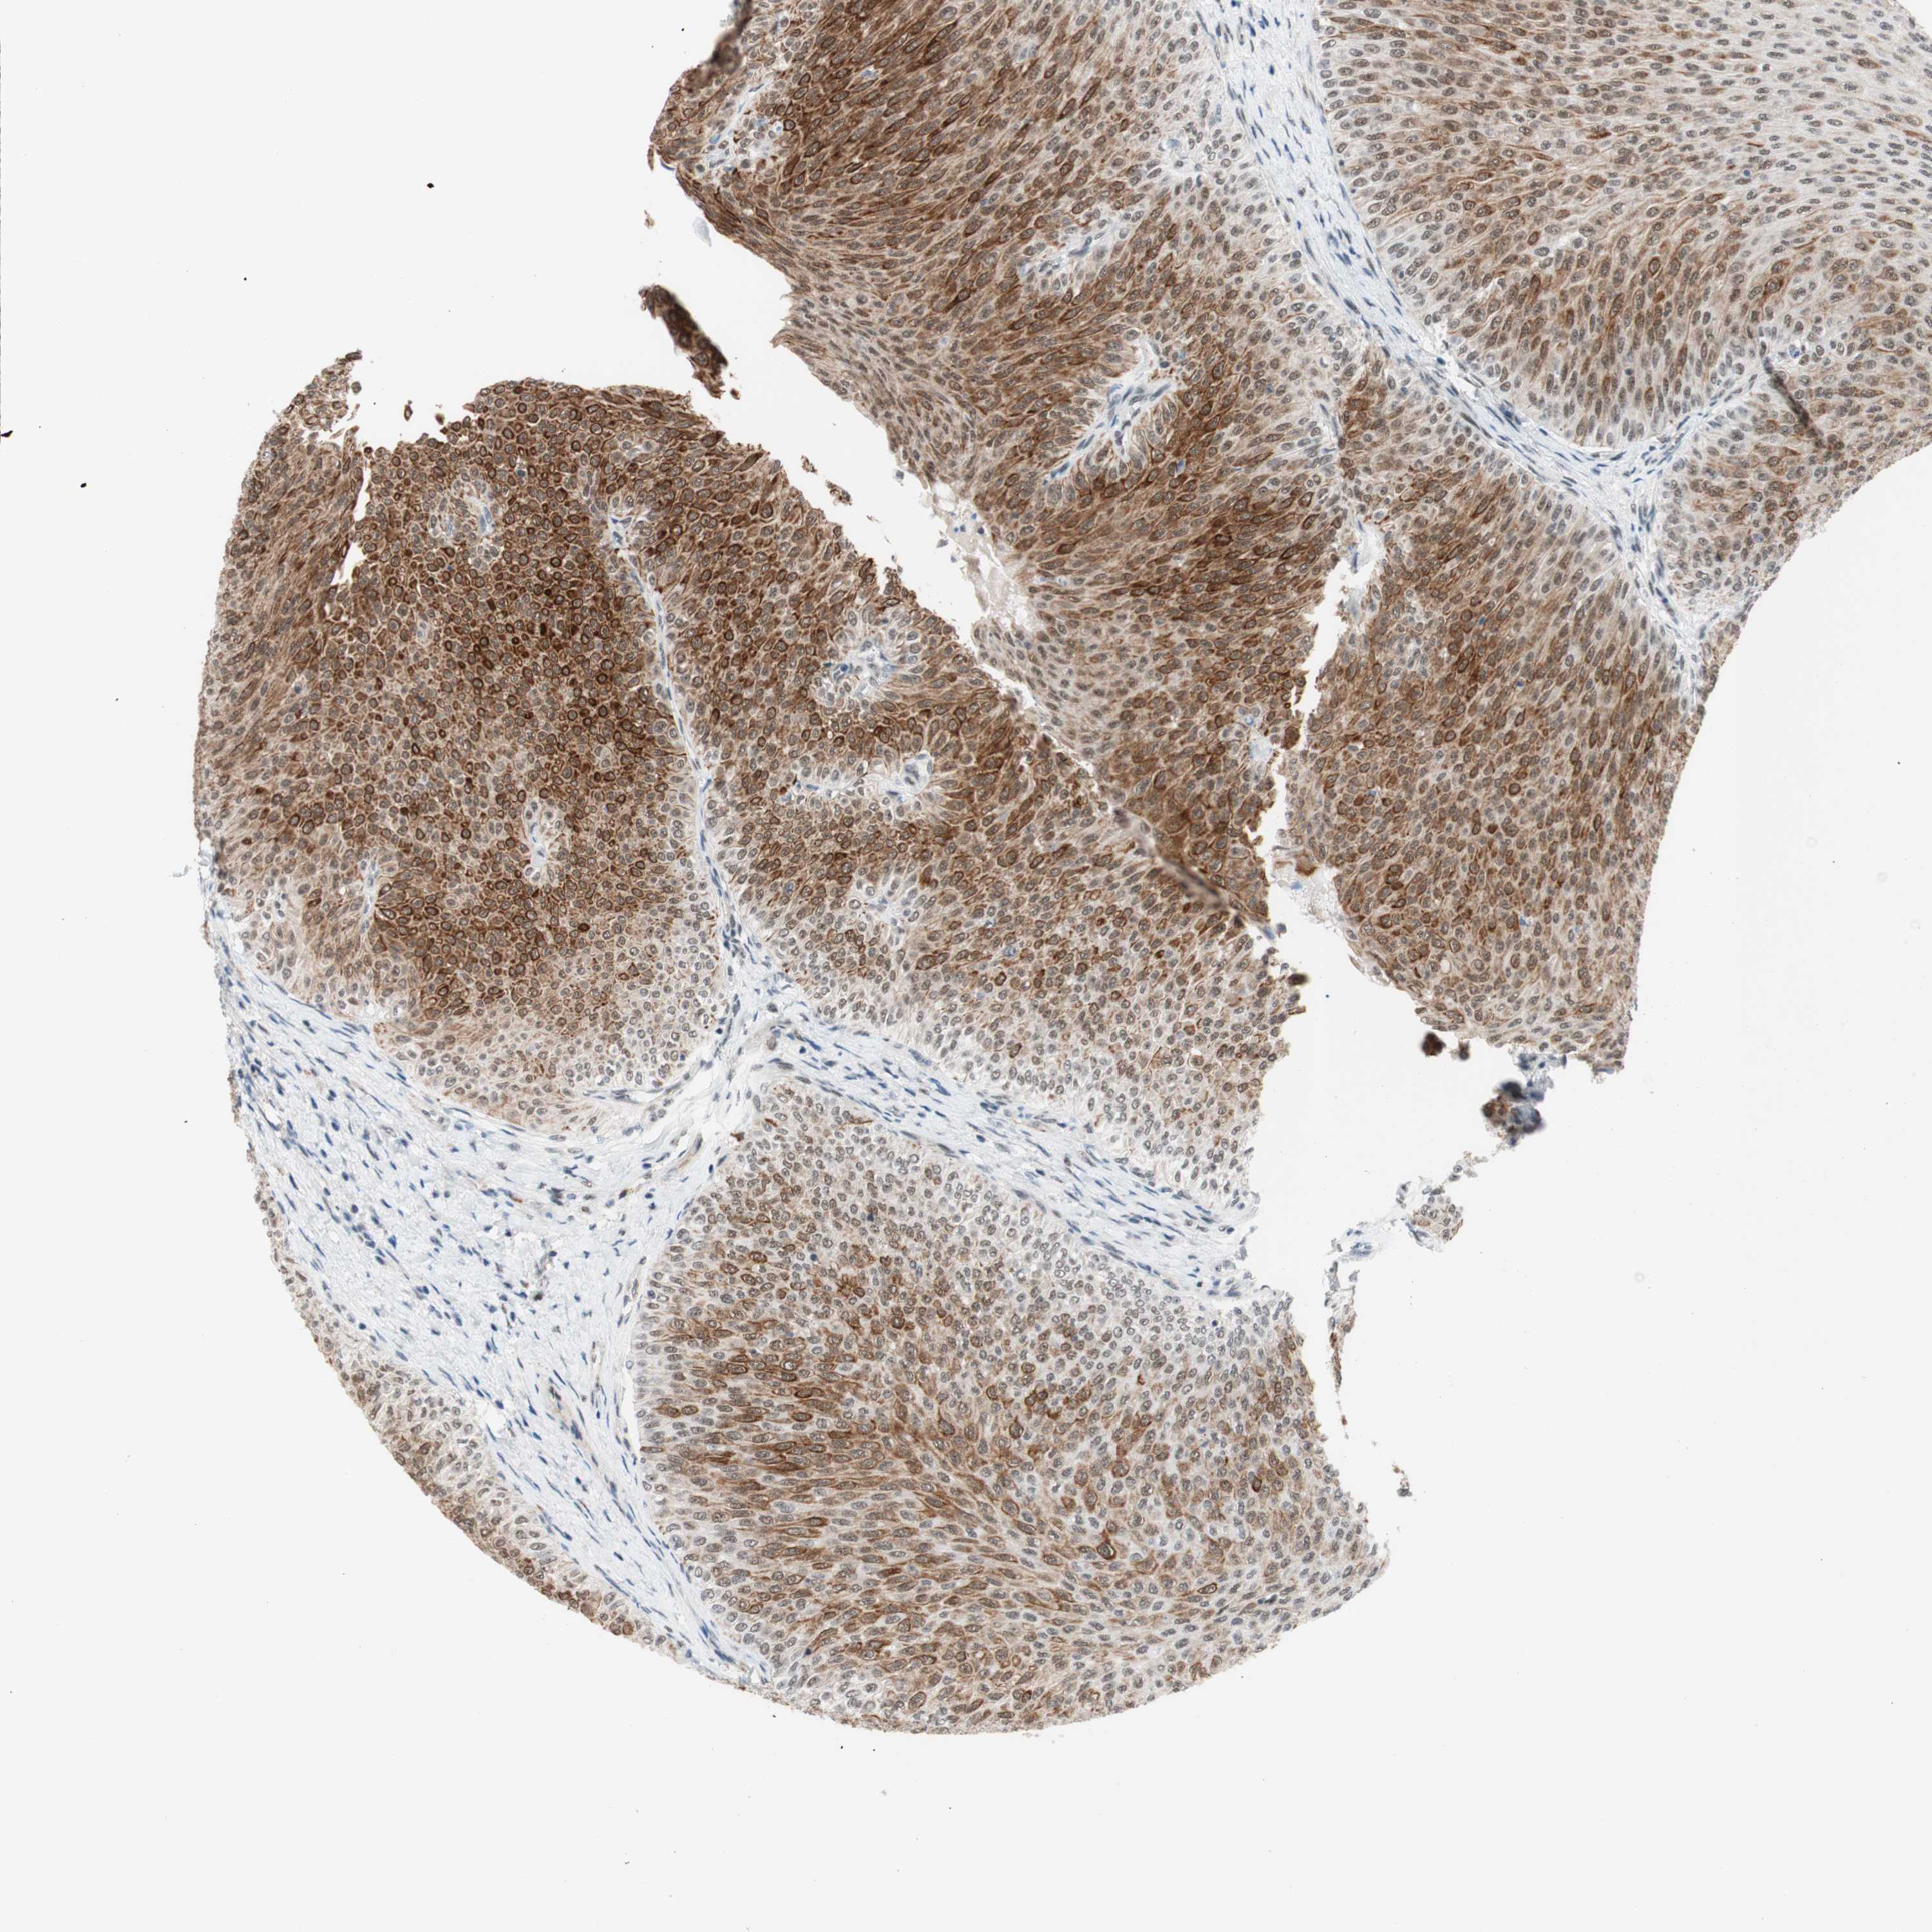

UROTHELIAL CANCER - Protein expressioni

A mouse-over function shows sample information and annotation data. Click on an image to view it in a full screen mode. Samples can be filtered based on level of antibody staining by selecting one or several of the following categories: high, medium, low and not detected. The assay and annotation is described here.

Note that samples used for immunohistochemistry by the Human Protein Atlas do not correspond to samples in the TCGA dataset.

Antibody stainingi

Antibody staining in the annotated cell types in the current human tissue is reported as not detected, low, medium, or high, based on conventional immunohistochemistry profiling in selected tissues. This score is based on the combination of the staining intensity and fraction of stained cells.

Each image is clickable and will lead to virtual microscopy that enables deeper exploration of all samples and also displays staining intensity scores, fraction scores and subcellular localization as well as patient and tissue information for each sample.

Antibody HPA038051

Antibody HPA059070

Antibody CAB012448

Staining

High

Medium

Low

Not detected

Intensity

Strong

Moderate

Weak

Negative

Quantity

>75%

75%-25%

<25%

None

Location

Nuclear

Cytoplasmic/membranous

Cytoplasmic/membranous,nuclear

Urothelial carcinoma, High grade

Urothelial carcinoma, Low grade

Urothelial carcinoma, NOS